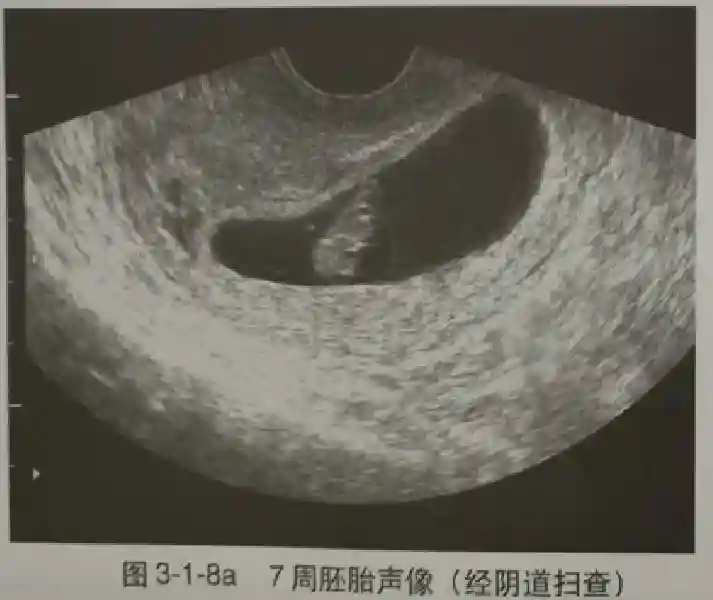

3️⃣胚胎:胚胎通常在6-7周时可以为超声显示,起初为胎芽,表现为卵黄囊一侧局部组织增厚,达到1 -2 mm 时才有可能为超声测量出来。达4-5mm时可见胎心搏动,相应孕周为6-6.5周,妊娠囊大小为13-18mm。胚芽长度≥7㎜时仍未见心管搏动,提示胚胎停止发育。胚胎的出现和妊娠囊直径的关系:妊娠囊直径> 16 mm 时,经阴道超声应显示胚胎。妊娠囊直径> 25 mm 时,经腹超声均应显示胚胎。

5️⃣羊膜:早孕期羊膜囊菲薄,超声常不能显示。孕7周以后加大增益或者用高频超声可以显示羊膜。羊膜囊位于绒毛膜内,胚胎位于羊膜囊内。随着胚胎增长,羊水增多,羊膜囊增大,孕12-16周时,羊膜与绒毛膜全部融合,胚外体腔消失。宫腔线一侧内膜内一圆形增强回声区,中央有小囊状液性暗区,宫腔线局部突起变形,称蜕膜内征,用于判断早早孕。

5️⃣羊膜:早孕期羊膜囊菲薄,超声常不能显示。孕7周以后加大增益或者用高频超声可以显示羊膜。羊膜囊位于绒毛膜内,胚胎位于羊膜囊内。随着胚胎增长,羊水增多,羊膜囊增大,孕12-16周时,羊膜与绒毛膜全部融合,胚外体腔消失。宫腔线一侧内膜内一圆形增强回声区,中央有小囊状液性暗区,宫腔线局部突起变形,称蜕膜内征,用于判断早早孕。#超声 #早孕检查 #妊娠